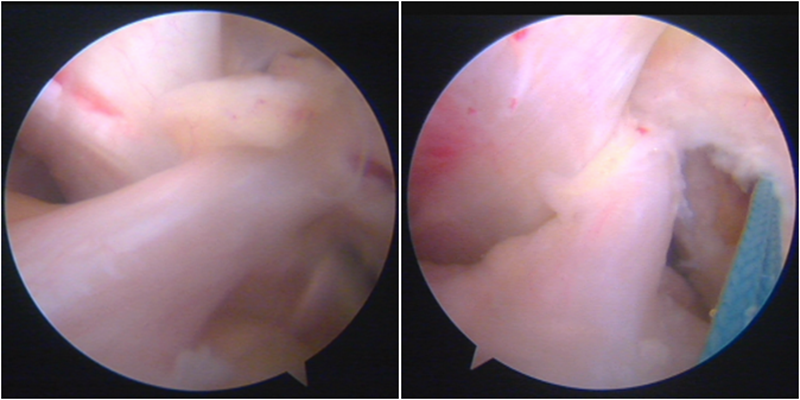

保残重建关节镜下分型:

将保残重建分为保留残束、残端和残根3种类型。

残束:是指ACL的前内侧束或后外侧束的某一束损伤,而另一束的解剖结构 还存在;

残端:是指 ACL 在股骨附着点撕脱后,仍然保留 ACL 的基本形体和长度但没有张力;

根:是指损伤后 ACL 断端吸收或缺如,有的在胫骨止点留有ACL的残迹。

镜下显示ACL残束

内侧半月板

外侧半月板